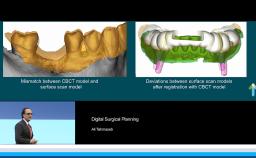

Surgical Planning and Procedures

- Surgical considerations regarding the type of bone augmentation procedure and the timing of implant placement.